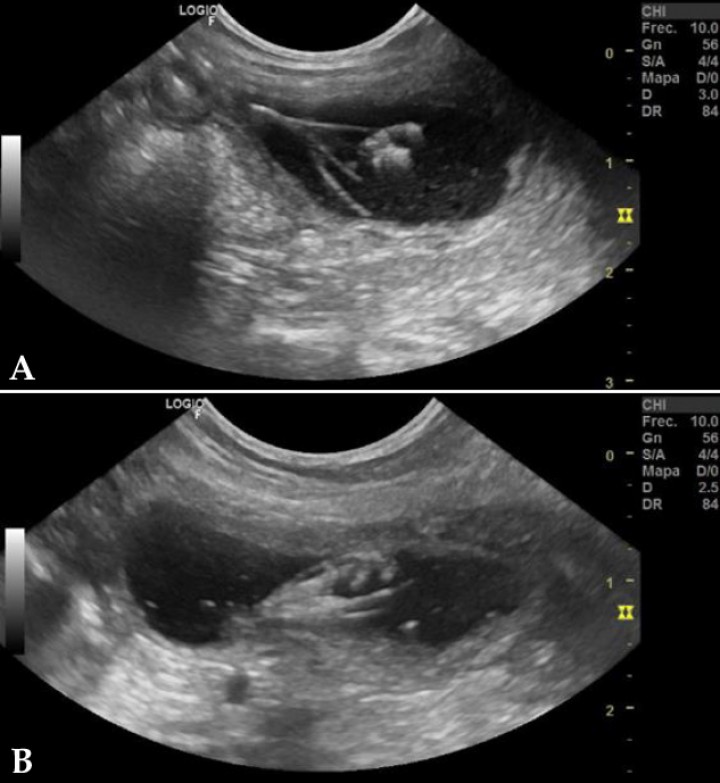

Los resultados de la analítica sanguínea estaban dentro de la normalidad, con excepción de una uremia leve (30 mg/dl; valor de referencia: 7-27 mg/dl). El estudio radiográfico y ecográfico abdominal solo evidenció un foco hiperecoico con un cono de sombra acústica asociado a la unión corticomedular del riñón derecho compatible con una posible calcificación (Fig. 1). La vejiga no pudo ser valorada al presentarse vacía, no pudiéndose realizar cistocentesis para hacer cultivo de orina (Fig. 2).

<p>Imagen de un corte sagital del riñón derecho, en el que puede apreciarse una estructura hiperecogénica en la zona de la pelvis renal.</p>

Figura 1

Imagen de un corte sagital del riñón derecho, en el que puede apreciarse una estructura hiperecogénica en la zona de la pelvis renal.

<p>Corte sagital de la vejiga de orina, en el que podemos apreciar la inexistencia de suficiente orina para ser valorada correctamente.</p>

Figura 2

Corte sagital de la vejiga de orina, en el que podemos apreciar la inexistencia de suficiente orina para ser valorada correctamente.